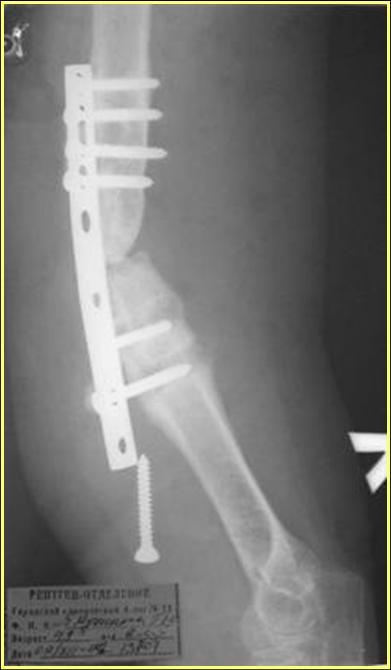

Типичная положительная ситуация для интрамедуллярного остеосинтеза с

использованием опорного металлокаркаса для компенсации дефекта.

Рентгеновская версия реконструкции. хронология:

после операции, 2 мес. после операции, через 1 год

Движения в полном объеме восстановлены к 2 мес. после операции. Если надо могу показать мультик. Сейчас уже прошло более 3 лет, больная не